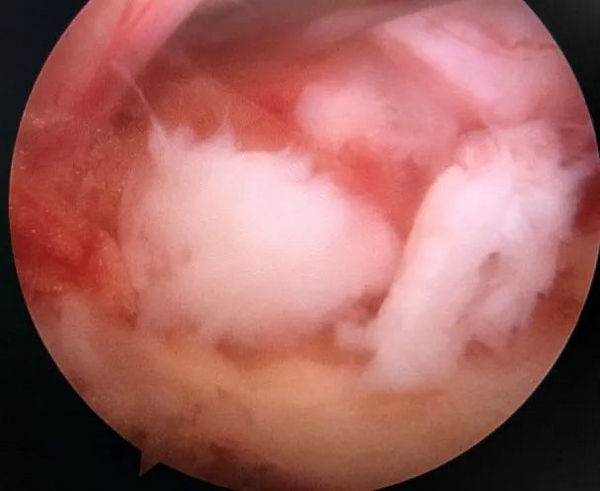

髓核摘除前后对比

患者接受手术治疗,术中仅通过两个长约0.5cm及1cm的手术切口,置入脊柱内镜及操作器械,逐步扩大“狭窄的椎管”并顺利摘除“脱出的椎间盘组织”,解除神经受压情况。

3.切除黄韧带

4.显露椎间盘

5.摘除髓核